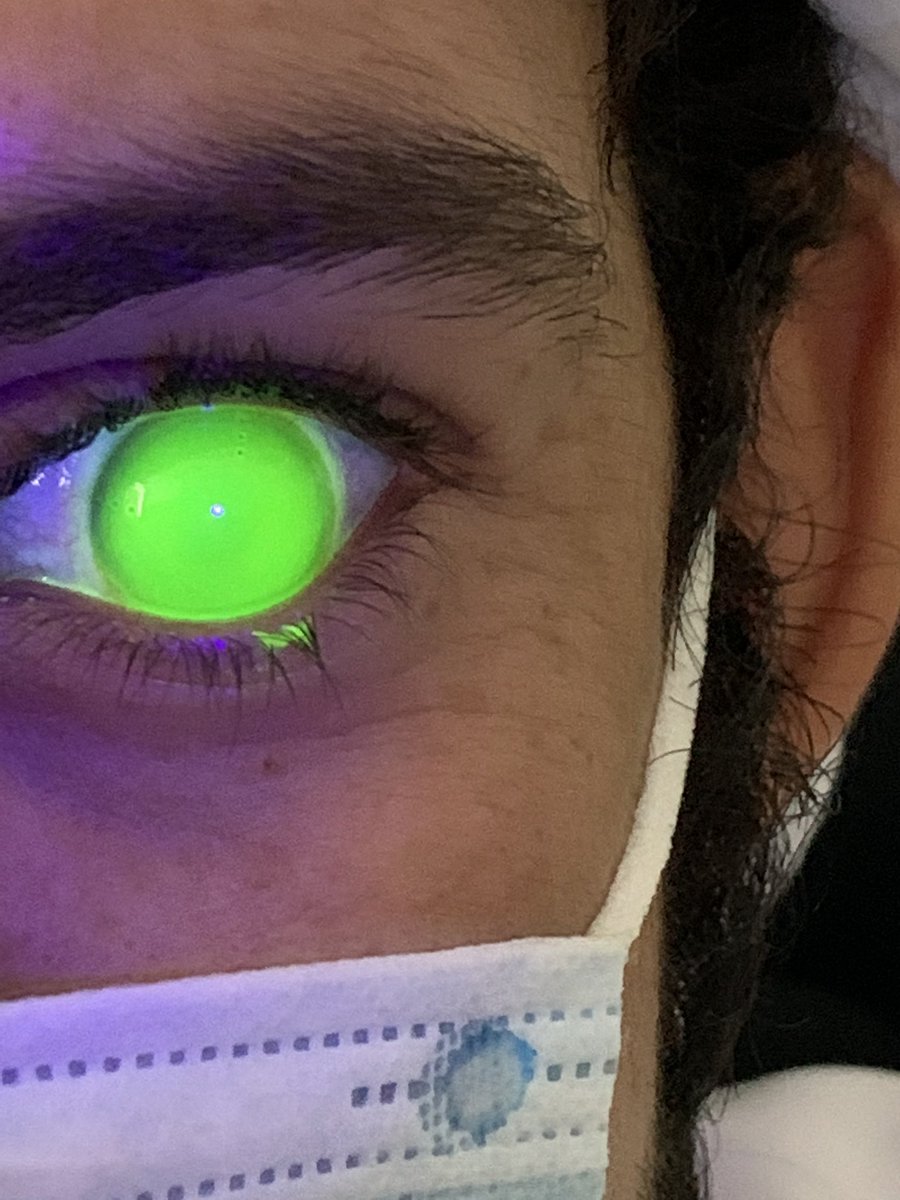

القرار طبعا في تلك الفتره ، اولا يتوقف عن العدسات اللينه الغير ملائمه ، كورس ادويه عباره عن قطرات مرطبه ومضادات للتحسس وتجربه عدسات scleral ، بعد اسبوعين وعند وصول العدسات كانت العيون هدت شوي وبدت بمرحله التعافي مع استخدام العدسات الجديده والحمدلله مع نظر مميز ،،

بعد العمليه النظر في العين اليمين تحسن كثير وصار قريب من 6/12 ولكن العين اليسار للاسف ما صار فيها تحسن !! وصار يعاني من عدم توازن في الرؤيه وكراهيه للضوء ومستمر على قطرات ضغط العين ،،